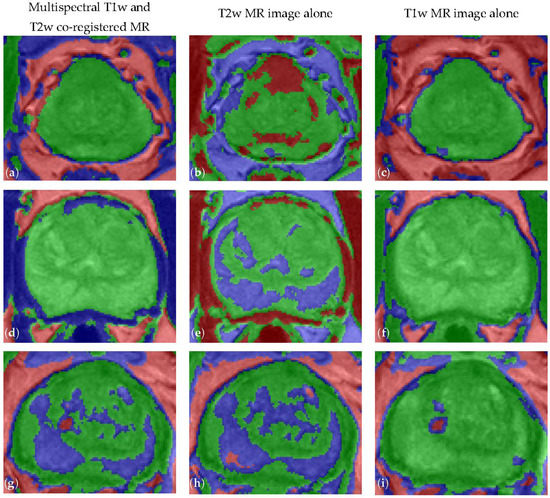

| MRI Data | DSC | JI | Sensitivity | Specificity | FPR | FNR |

|---|---|---|---|---|---|---|

| Multispectral | 90.77 ± 1.75 | 83.63 ± 2.65 | 89.56 ± 3.02 | 99.85 ± 0.11 | 0.15 ± 0.11 | 6.89 ± 3.02 |

| T2w alone | 81.90 ± 6.49 | 71.39 ± 7.56 | 82.21 ± 8.28 | 99.63 ± 0.25 | 0.37 ± 0.25 | 12.58 ± 8.49 |

| T1w alone | 82.55 ± 4.93 | 71.78 ± 6.15 | 93.27 ± 4.87 | 98.85 ± 0.58 | 1.15 ± 0.58 | 3.58 ± 4.95 |

| MRI Data | MAD (pixels) | MaxD (pixels) | HD (pixels) |

|---|---|---|---|

| Multispectral | 2.676 ± 0.616 | 8.485 ± 2.091 | 4.259 ± 0.548 |

| T2w alone | 4.941 ± 1.780 | 13.779 ± 3.430 | 4.535 ± 0.335 |

| T1w alone | 5.566 ± 1.618 | 14.358 ± 3.722 | 5.177 ± 0.857 |